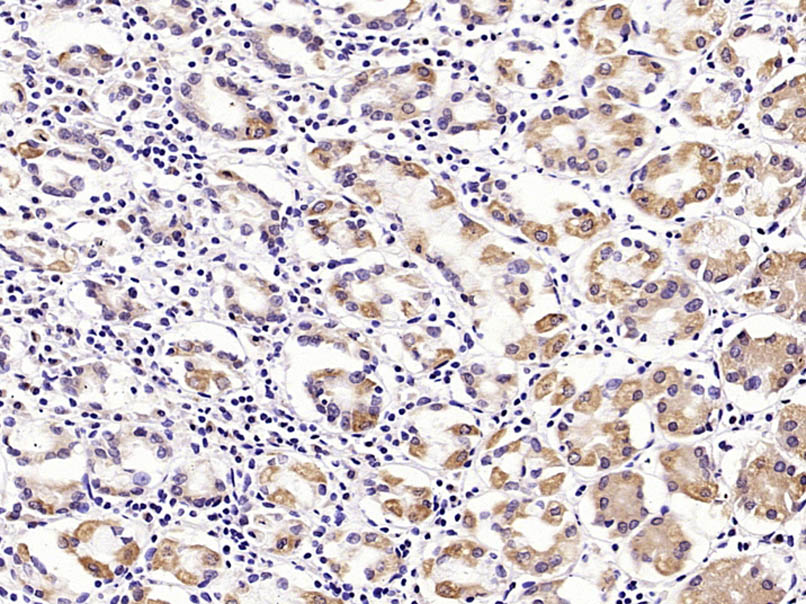

Paraformaldehyde-fixed, paraffin embedded (mouse stomach tissue); Antigen retrieval by boiling in sodium citrate buffer (pH6.0) for 15min; Block endogenous peroxidase by 3% hydrogen peroxide for 20 minutes; Blocking buffer (normal goat serum) at 37°C for 30min; Antibody incubation with (MUC5AC) Polyclonal Antibody, Unconjugated (bs-7166R) at 1:400 overnight at 4°C, followed by operating according to SP Kit(Rabbit) (sp-0023) instructionsand DAB staining.